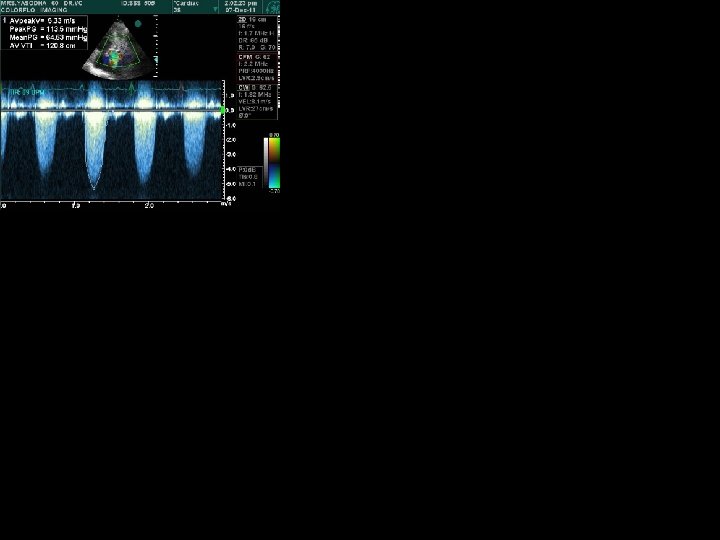

Cycle Length Variation Post premature beat / Long cycle short cycle of AF • Post VPD / Long > Short cycle of AF : Outflow murmurs ( AS/PS) accentuate Regurgitant murmurs do not change

Aortic Stenosis HOCM